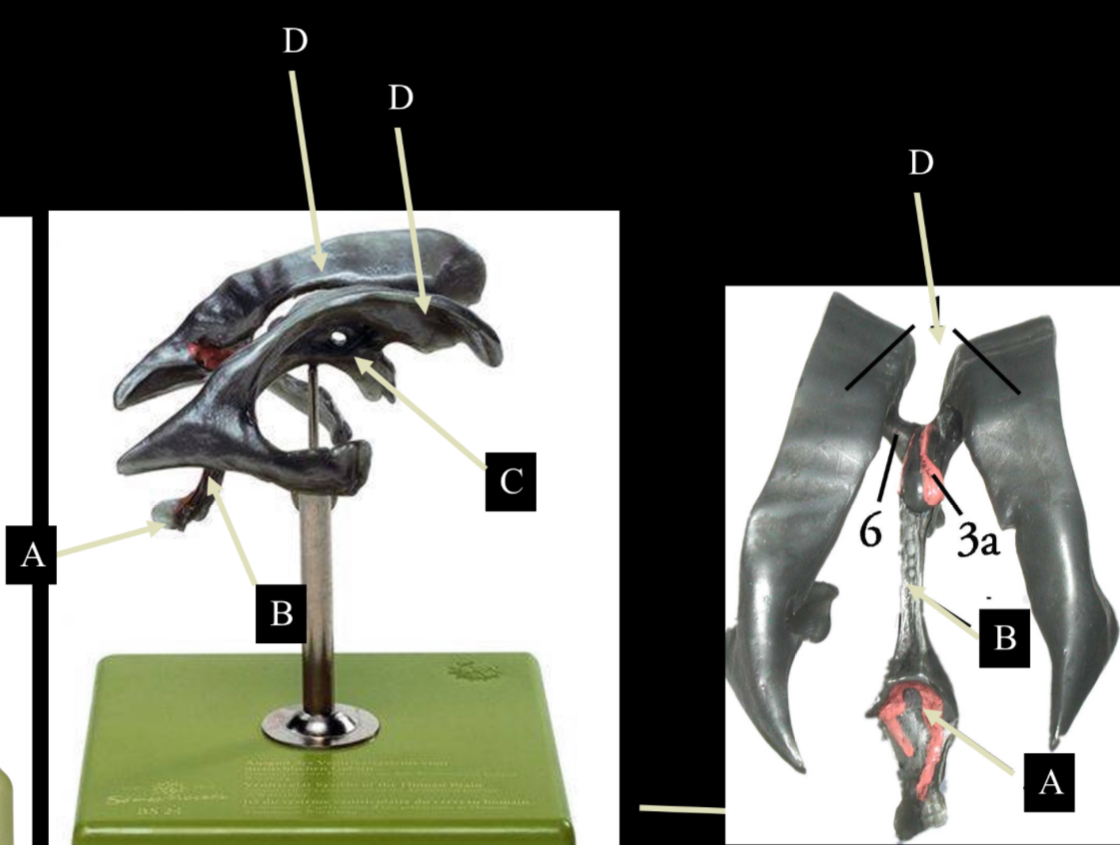

What is D?

lateral ventricle

Imagine thin membrane separating the 2 lateral ventricles

septum pellucidum

What is C?

3rd ventricle

What is B?

cerebral aqueduct

What is A?

4th ventricle

What is below A at the very end?

central canal (spinal cord)